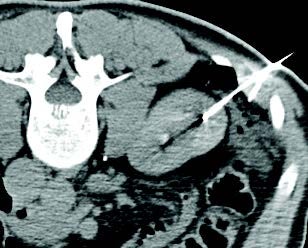

Celiac Plexus Cryoneurolysis case study

A 66-year-old man presented with intractable upper abdominal pain refractory to medical management with opiates. MRI axial images through the celiac plexus at the celiac plexus at the level of the celiac axis and SMA origins demonstrate bulky retroperitoneal adenopathy and soft tissue tumor infiltrate. Two IceRod™ 1.5 CX needles were placed within and along the bilateral celiac plexus via CT-guidance. The CT Axial image (right) in prone position shows right-sided iceball formation along the celiac plexus demonstrating excellent coverage. The patient reported pain at 2/10 after a 3-day follow-up pain assessment; the pain score before the procedure was a 10/10.

Aron Chary, MD I MidSouth Imaging - Vascular Interventional Physicians I Memphis, TN